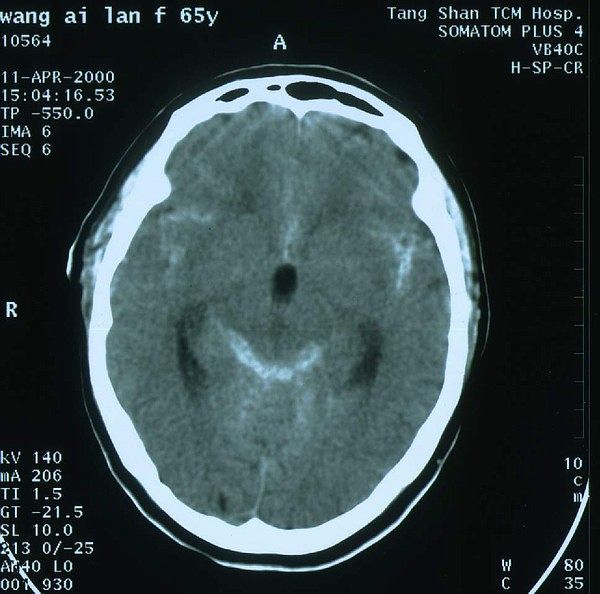

最直接最准确的诊断方法是全脑血管造影,因此被6称之为诊断动脉瘤的金标准。近几年神经影像学技术发展很快,像CT、磁共振血管造影检查也可以发现一部分颅内动脉瘤,而且没有创伤,但如果动脉瘤太小,就只能通过血管造像检查来确定。